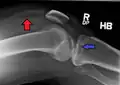

• Type II = Lateral tibial plateau fracture with depression,

This is a combined cleavage and compression fracture and involves vertical split of the lateral condyle combined with depression of the adjacent load bearing part of the condyle. Caused by a valgus force on the knee; it is a low energy injury, typically seen in individuals of the 4th decade or older with osteoporotic changes in bone. Most common, and make up 75% of all tibial plateau fractures. There is a 20% risk of distraction injuries to the medial collateral ligament. May include distraction injury to the medial collateral ligament or anterior cruciate ligament.

Lateral Tibial Plateau fracture XRay with Depression